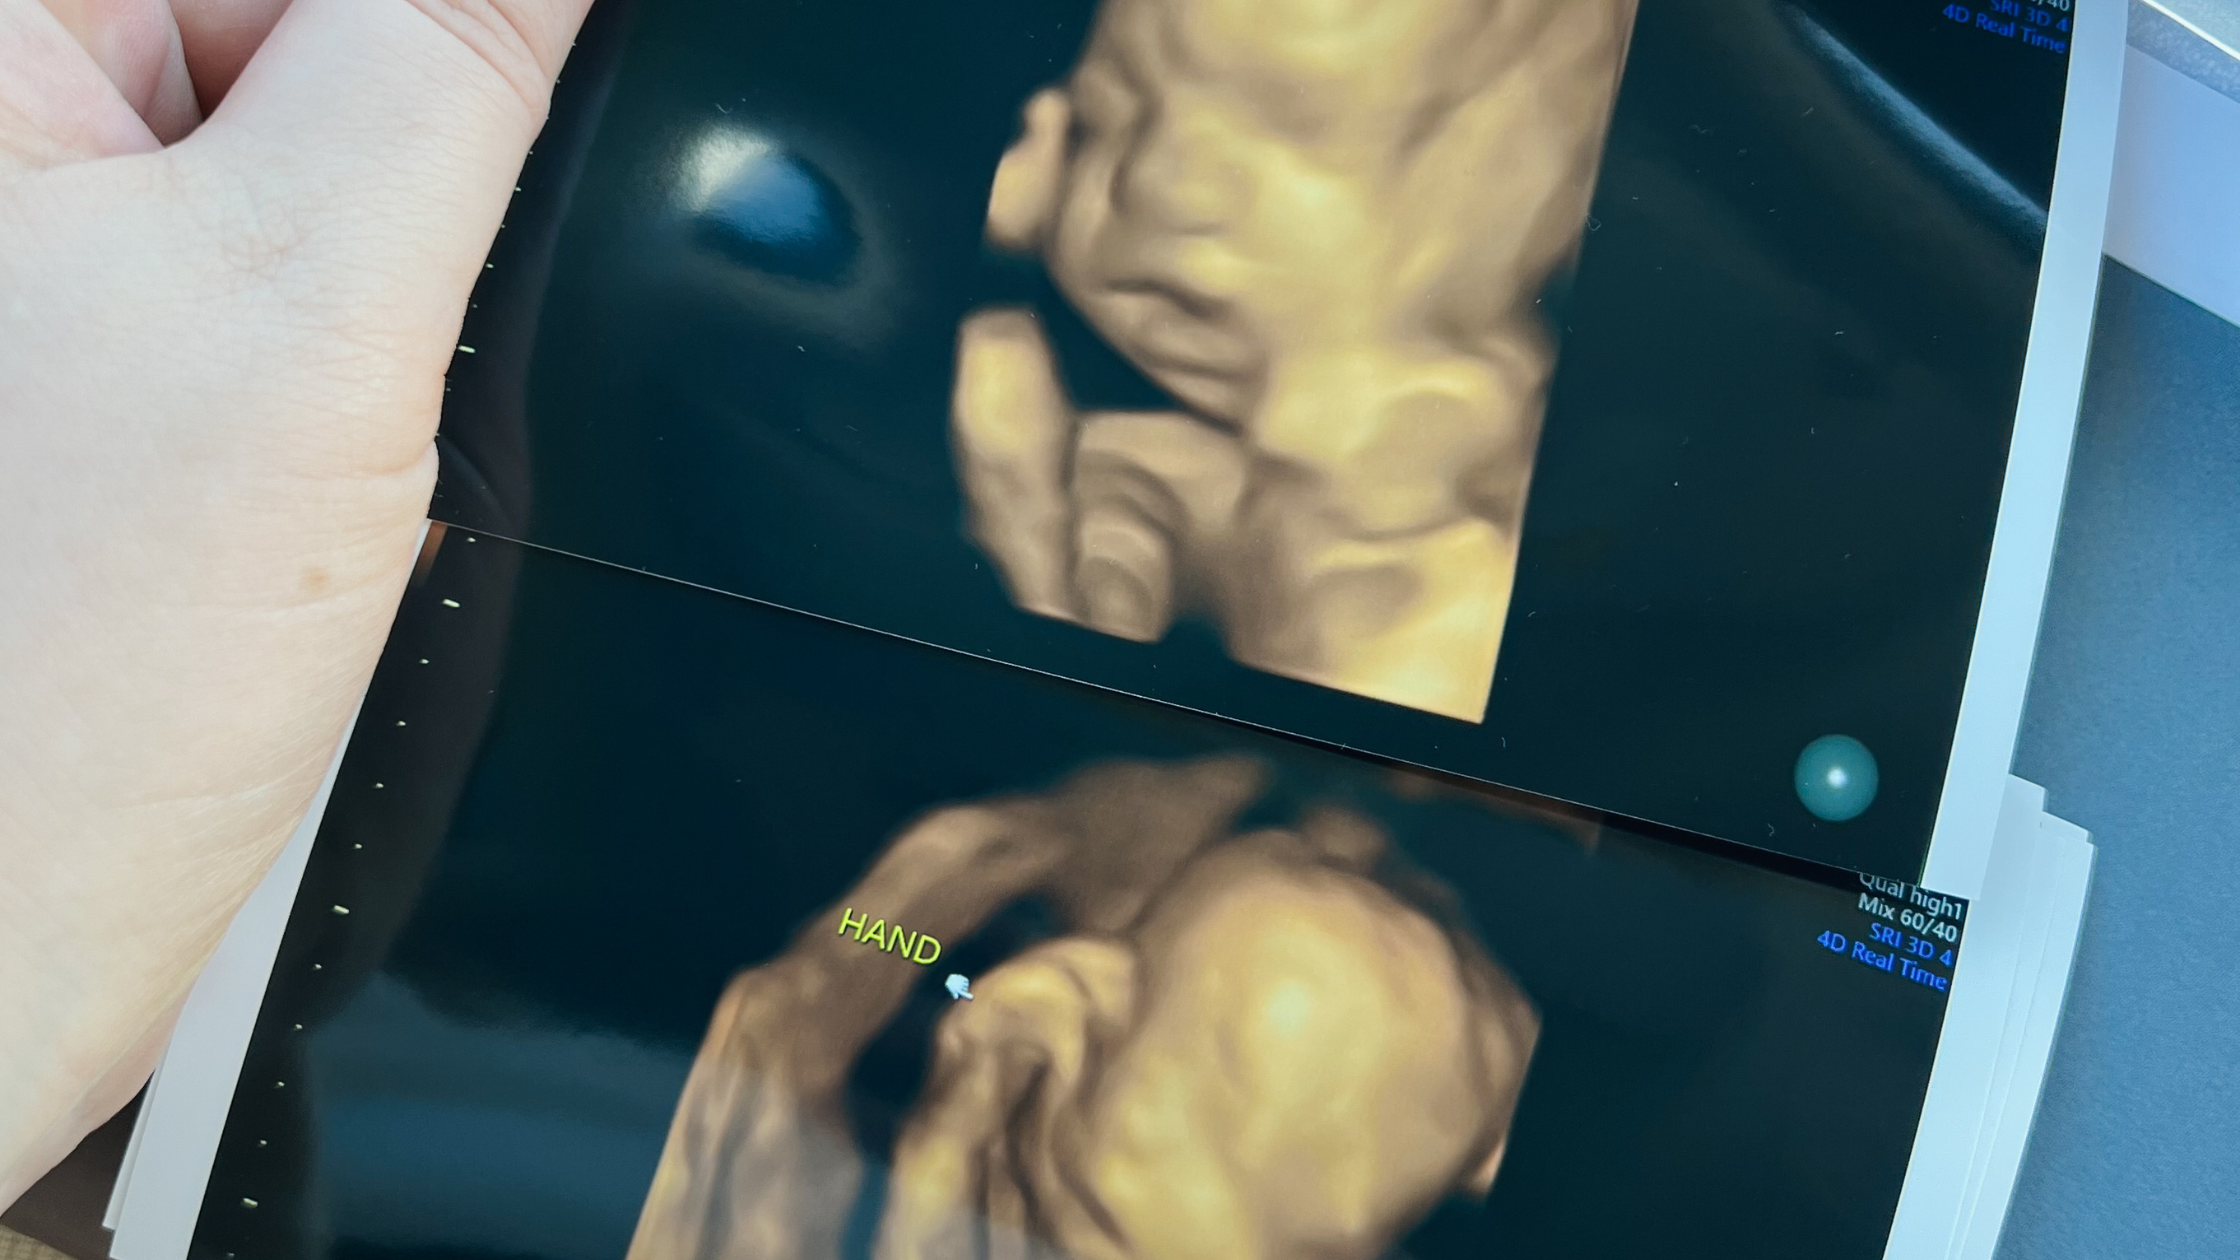

Pregnancy is a time filled with anticipation and excitement, and one of the most thrilling milestones is seeing your baby on an ultrasound. For many